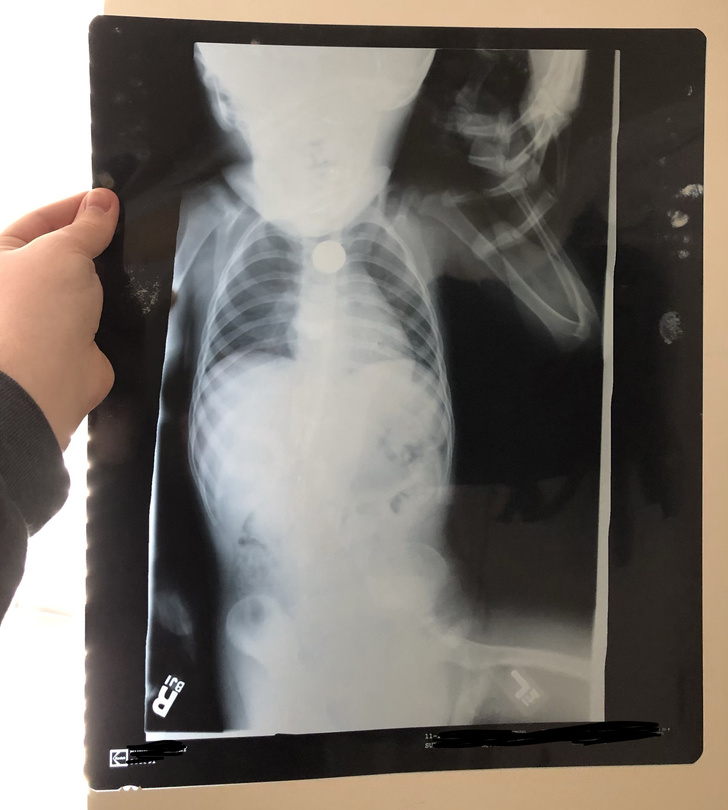

1. «На цьому рентгенівському знімку видно пенні, який я проковтнув, коли був маленький. І так, я тримаюся за мамину руку»